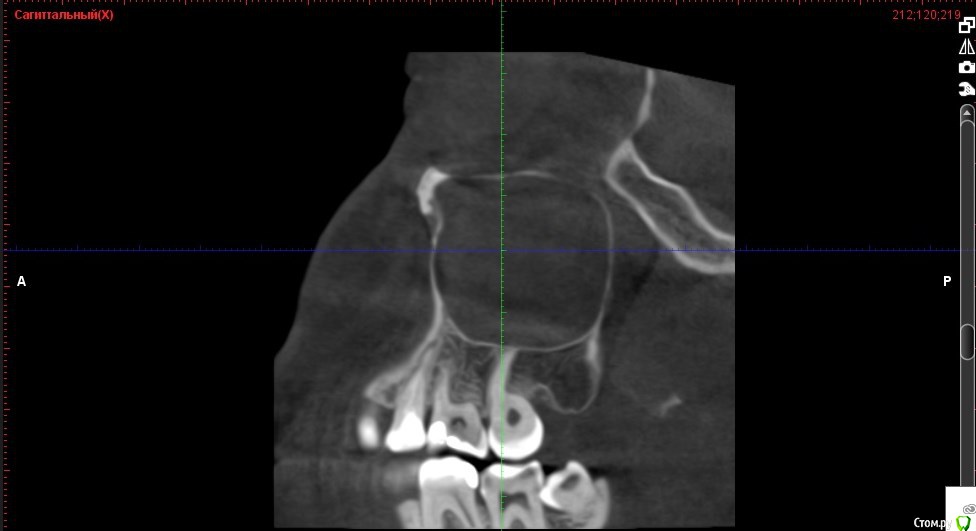

Verasss Опубликовано 8 октября, 2016 Автор Поделиться Опубликовано 8 октября, 2016 КТ от 08.09. Извините, что в таком виде, надо менять ОЗУ. Ссылка на комментарий

DmitrySH Опубликовано 8 октября, 2016 Поделиться Опубликовано 8 октября, 2016 В таком виде КТ малоинформативно. Но гайморита нет. Ссылка на комментарий

Verasss Опубликовано 28 октября, 2016 Автор Поделиться Опубликовано 28 октября, 2016 Добрый вечер! Ещё раз попытаюсь прикрепить скриншоты КТ от сентября. Если качество совсем не устраивает, подскажите, пожалуйста, какие сделать снимки?К сожалению, программа не позволяет вывести снимки на полный экран и заскриншотить в более хорошем качестве. Ссылка на комментарий

Verasss Опубликовано 28 октября, 2016 Автор Поделиться Опубликовано 28 октября, 2016 еще снимки Ссылка на комментарий

Verasss Опубликовано 28 октября, 2016 Автор Поделиться Опубликовано 28 октября, 2016 и еще Ссылка на комментарий